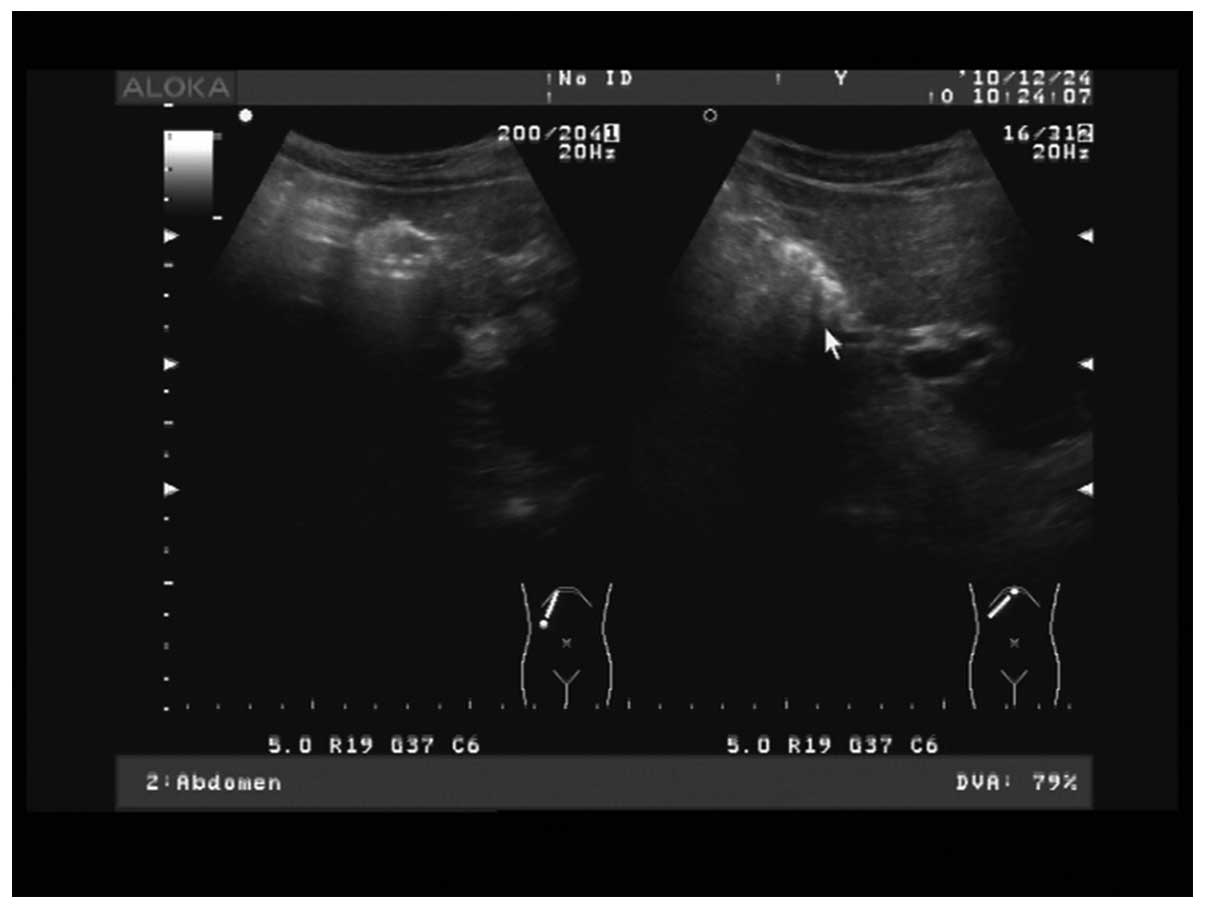

Figure 1.

Ultrasound showing the absence of bile echo in the gallbladder in visible outline, gallbladder contraction, and high echo.

Upon auxiliary examination, color Doppler ultrasound of the abdomen indicated chronic atrophic cholecystitis with gallbladder stones. Fig. 1 shows a color Doppler ultrasound of the congenital ASD, atrial septum consistency degradation, echo loss of 50 mm, large left-to-right shunt volume and a flow rate of 0.73 m/sec. Figs 2 and 3 show the left anterior descending artery examination results, which identified that the patient was positive for Hepatitis C virus antibody, while the results of routine blood test and biochemistry were normal.